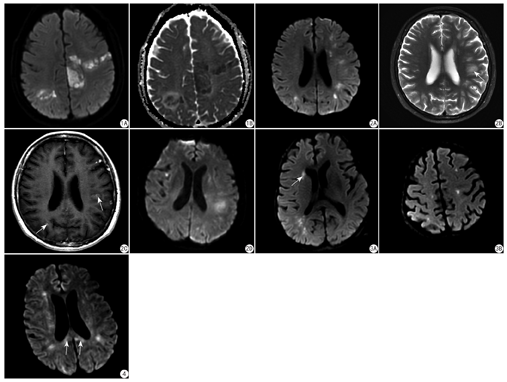

4例患者均可见脑内明显异常,呈多发病变,DWI上类似脑梗死病灶,表现为斑片状或点状的高信号(图1,图2,图3,图4),ADC图上呈稍低信号(图1B)。在T2WI或FLAIR像上,病灶呈稍高信号,与DWI像比较,T2WI上显示的病灶范围更大,而且显示了更多的病灶(DWI上未显示,图2B)。T1WI上较大的病灶呈低信号,小病变信号变化不明显,常不显示。本组4例患者脑内病灶的分布均无法用单一血管分布区解释,均可见大脑半球白质的受累,其中2例累及基底节(图3A)、1例累及双侧小脑半球,1例累及胼胝体(图4)。

本组4例患者,有两例(Case1、Case2)出现强化,Case1左中央旁小叶病灶内出现小片状轻度强化,余病灶无强化。Case2表现为多发强化灶,呈斑片或斑点状,强化灶的位置出现在T2WI高信号区,与DWI高信号并不一致(图2B、图2C)。4例均未见脑膜强化。

Case1进行了MRS、ASL和SWI检查,MRS (左中央旁小叶病变采样)显示N-乙酸门冬氨酸(N-acetylaspartate,NAA)减低(提示神经元受损),胆碱(choline,Cho)轻度升高(提示细胞活跃),可见巨大的乳酸峰。SWI上左中央旁小叶病变内见低信号。ASL显示所有病变区均为低灌注。Case 4进行了MRS检查,在DWI高信号病变区采样,显示NAA略减低,Cho轻度升高,有小的脂峰和乳酸峰。

3例病变在活检前进行多次MRI检查,DWI上均可见新的高信号病变出现,原DWI上高信号病变范围可见部分增大,部分消失,呈"此起彼伏"表现。其中一例强化灶肉眼可见显著的增大(间隔1个月复查)。4例均在活检明确诊断IVL后进行了化疗。3~6个月随访可见DWI病变均消失,强化灶消失,部分较大病变遗留软化灶。双侧脑室旁白质出现对称的、不同程度的T2/FLAIR高信号,伴不同程度的脑组织萎缩(脑室、脑沟扩大)。